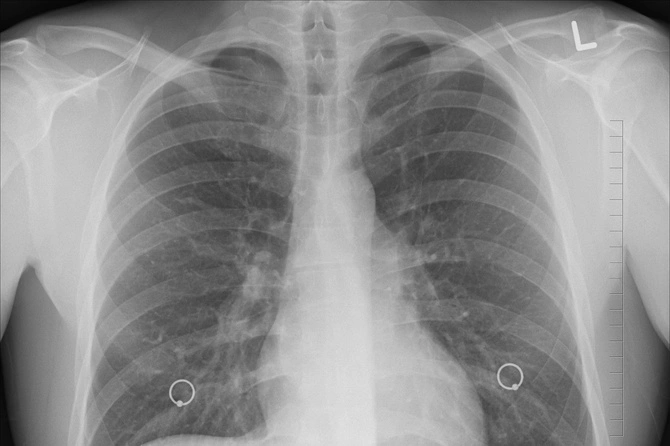

Член-корреспондент РАН, главный врач онкоцентра Лапино-2, доктор медицинских наук Михаил Давыдов рассказал, что основными симптомами рака легких являются кашель, одышка и осиплость голоса.

«Осиплость голоса без причины — самый характерный признак рака легкого. Она появляется из-за прорастания раковой опухоли в возвратный гортанный нерв. Но появляется этот симптом уже тогда, когда заболевание серьезно запущено. На более ранних этапах симптомом может быть кашель и периодическая одышка. Не все обращают внимание на них, особенно сейчас, в период пандемии COVID-19», — сказал он «Газете.ru».